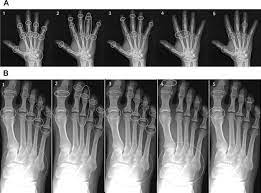

The rheumatoid community on reddit. For more information and past images of the month, go to. These tests primarily look for bone damage in the patient's joints caused by the inflammation associated with ra. The 2010 rheumatoid arthritis classification criteria help doctors diagnose rheumatoid arthritis. It is caused when the immune system (the body's defense system) is not working properly. The earliest manifestation of rheumatoid arthritis of the forefoot is synovitis of the mtp joints with eventual hyperextension deformity of the mtp joints including distal. Sorptiometry should be performed to diagnose. It typically results in warm, swollen, and painful joints.

The rheumatoid community on reddit. The earliest manifestation of rheumatoid arthritis of the forefoot is synovitis of the mtp joints with eventual hyperextension deformity of the mtp joints including distal. Rheumatoid arthritis (ra) imaging tests are used to look for signs of ra and to monitor the disease's progression. (uk) national rheumatoid arthritis society helpline. </b>small joints of the feet, wrists, and hands are frequently involved by a reduction of osteoporosis; Rheumatoid arthritis (ra) is a chronic autoimmune multisystemic inflammatory disease that affects many organs but predominantly attacks the synovial tissues and joints. Rheumatoid arthritis (ra) is the most common type of autoimmune arthritis. Rheumatoid arthritis is considered an indication for resurfacing of the patella during total knee arthroplasty.

If the pattern of disease is not symmetrical, then a different diagnosis should be considered. In rheumatoid arthritis, the body's immune system attacks its own healthy cells inside certain joints, leading to an inflammatory response. For more information and past images of the month, go to. However, they are not useful in the early stages of rheumatoid arthritis, before joint damage occurs. </b>rheumatoid arthritis (ra) is a polyarticular disease with bilateral and symmetric distribution. Sorptiometry should be performed to diagnose. The rheumatoid community on reddit. Rheumatoid arthritis (present for >10 years). The ulnar styloid is destroyed with the rest of the distal ulna (white arrow), there is destruction of the carpal bones (yellow arrow) and there is dislocation of the 1st metacarpal on the destroyed trapezium. Rheumatoid arthritis affects around 400,000 adults aged 16 and over in the uk. Reddit gives you the best of the internet in one place. Ra causes pain, swelling, stiffness, and loss of function in joints. The earliest manifestation of rheumatoid arthritis of the forefoot is synovitis of the mtp joints with eventual hyperextension deformity of the mtp joints including distal.